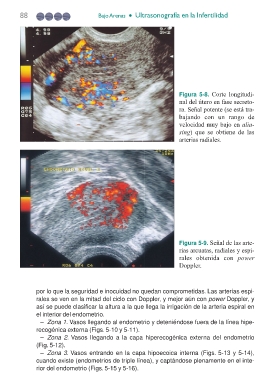

Figura 5-8. Corte longitudi-

nal del útero en fase secreto-

ra. Señal potente (se está tra-

bajando con un rango de

velocidad muy bajo en alia-

sing) que se obtiene de las

arterias radiales.

Figura 5-9. Señal de las arte-

rias arcuatas, radiales y espi-

rales obtenida con power

Doppler.